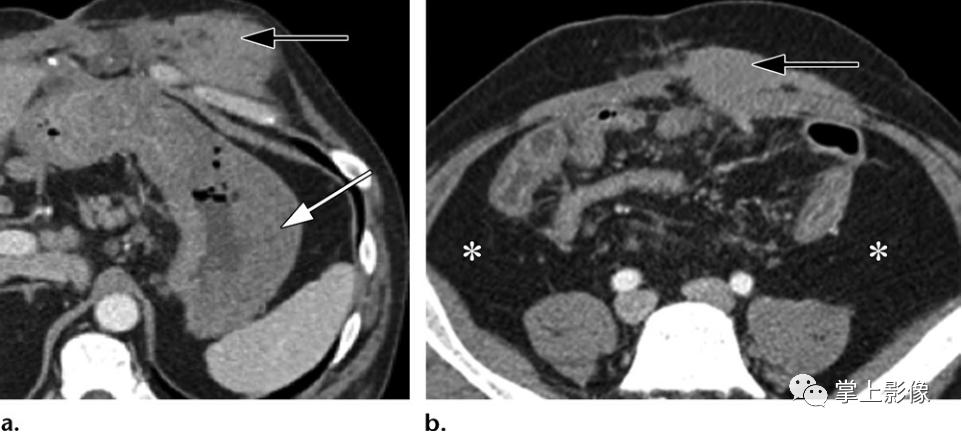

莫雷尔-拉瓦莱损伤(morell-avallee),50岁男性行人,被机动车撞到。轴位(A)和冠状位重建(B)CT图像显示闭合性脱套伤,从右下胸壁延伸至右侧髋部最尾侧,皮下积聚气体(黑色箭头)和液体(白色箭头a)集中在右侧腹壁。冠状重建图像显示了Morel-Lavallee病变的范围和两个移位的前外侧肋骨骨折(b方形轮廓)以及继发于移位的胸骨骨折(未显示)和纵隔气肿(b方形轮廓)。右腹股沟疝显示部分充气小肠环(b中白色箭头)。未见腹内脏器损伤

34岁加德纳综合征合并多发性腹部肿块的硬纤维样肿瘤。轴位增强CT图像显示肿块(黑色箭头)集中在腹直肌下方,外观与韧带样肿瘤最为一致。胃肿块(a中的白色箭头)后来被诊断为腺癌,注意到与以前的结肠切除术相比的变化(b中的*)